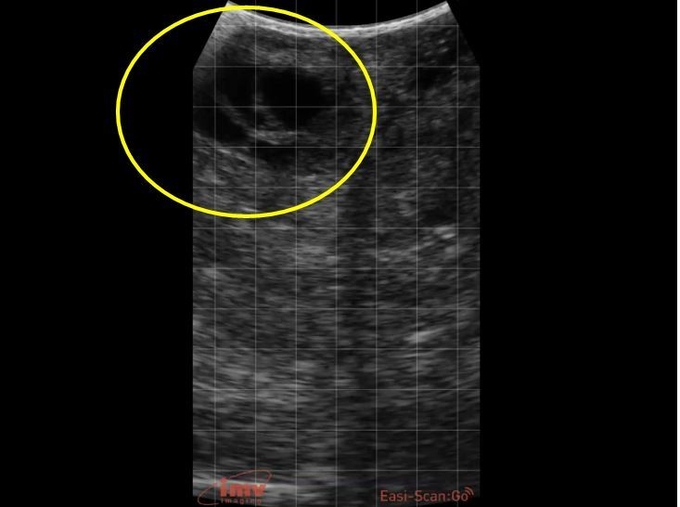

2. 직장초음파 영상으로 보는 모돈의 번식기관의 정상 사진과 대비되는 질병 초음파 영상

모돈의 번식질환은 번식과 관련한 기관별로 주요 번식질환을 구분할 수 있다. 기관별로 자주 발생하는 번식기관 문제와 진단된 초음파 영상을 보도록 하자.

①난소